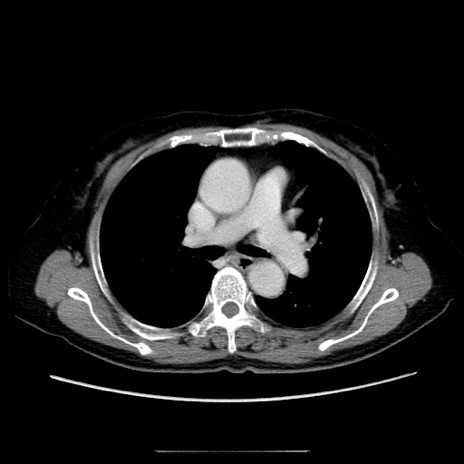

症例5(横断像)

【症例】70歳代女性

【主訴】お腹が張る

【現病歴】1週間くらい前から腹部膨満の自覚あり。昨日夜から増悪したため、本日救急外来受診。

【身体所見】意識清明、BT 36.5℃、BP 165/106mmHg、HR 80bpm、SpO2 98%、腹部:膨満、軟、自発痛・圧痛なし、触診にて不快感あり、腸蠕動音:減弱

【データ】WBC 12600、CRP 1.04